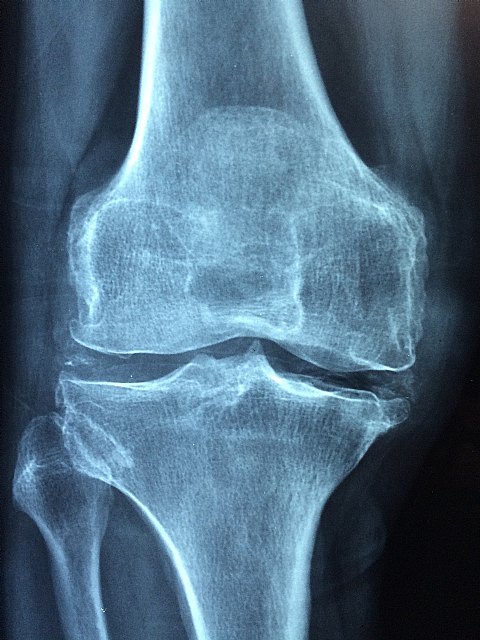

La osteoporosis es un trastorno generalizado del esqueleto muy prevalente -afecta a tres millones de personas en España-, en el cual existe una alteración de la resistencia ósea que predispone a la persona a un mayor riesgo de fracturas, especialmente en cadera, columna y muñecas. Es una de las enfermedades asociadas al envejecimiento, por lo que representa un problema de gran magnitud e importancia creciente.

Afecta tanto a mujeres como a hombres y, sus principales complicaciones, son la fractura vertebral (la más frecuente) y la fractura de cadera (la más grave). La incidencia de la fractura de cadera se sitúa en siete casos por cada 1.000 habitantes mayores de 65 años en España. "Requiere siempre de hospitalización y cirugía y, en fase aguda, tiene una mortalidad del 8% en España", según ha precisado el Dr. Óscar Torregrosa Suau, coordinador del Grupo de Trabajo de Osteoporosis de la SEMI, en la mesa "Nuevas Dianas Terapéuticas en osteoporosis y Vitamina D" del 41° Congreso de la Sociedad Española de Medicina Interna (SEMI).